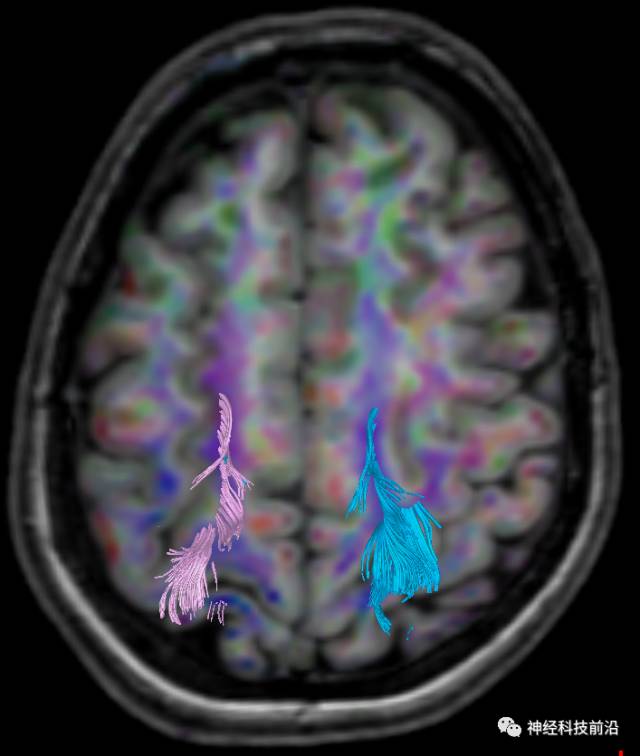

下面为皮质脊髓束的走形及位置